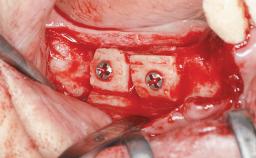

Le Fort I Interpositional Graft and Mandibular Sandwich Osteotomy for Maxillofacial Rehabilitation after Severe Periodontitis

A 47-year-old woman who had suffered from aggressive periodontitis requiring a number of periodontal interventions over more than 10 years was referred by her general dental practitioner and periodontologist for bone augmentation and implant therapy. Her failing dentition had already been scheduled for extraction. The patient expressed a desire for implant-supported fixed restorations and esthetic improvement of her lower face. She had agreed to consult with a maxillofacial surgeon after the referring dentist had suggested bone augmentation. An initial examination by the maxillofacial surgeon revealed mobility of all residual teeth in a patient who was very unhappy with the function of her removable partial dentures. Due to periodontally migrated flaring teeth and loss of occlusal support, the vertical dimension of occlusion was dramatically reduced. The patient was displeased with her lower face because of deepened nasolabial, commissural, and supramental folds.

Bone Augmentation Horizontal|Sinus Floor Elevation|Staged|Vertical

Augmentation Materials Autogenous chips|Autogenous block(s)|Xenogenous|Membrane